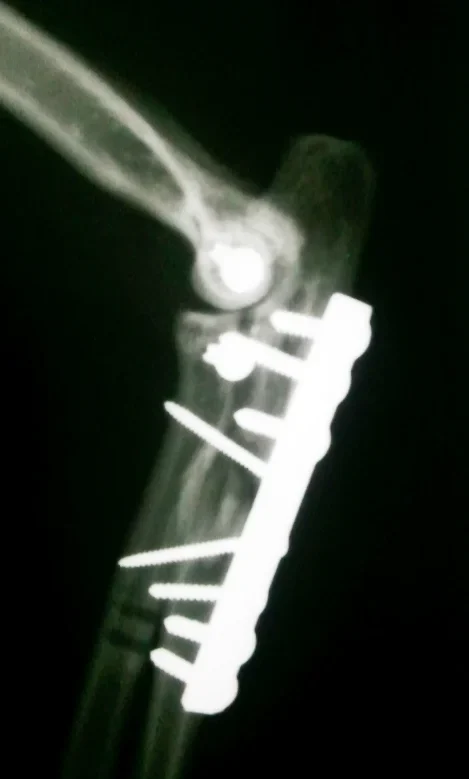

Galería de casos clínicos

Casos clínicos de cirugía (tejidos blandos, traumatología, neurocirugía, artroscopia)